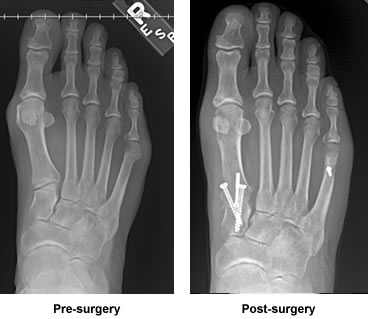

Dr. Leavitt performed bunion surgery on my right foot on both sides. He checked on me after surgery and told me to take care of his work and I did. I was non weight-bearing for 8 weeks. My hard cast was removed at about six weeks and a soft case applied for the remaining two weeks.